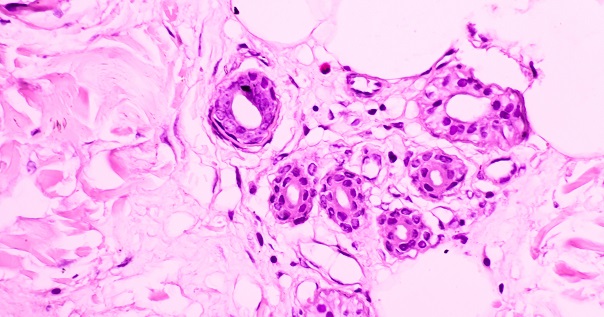

Разные клетки эпителия по-разному реагируют на повреждения, поэтому и опухоли выглядят неодинаково. Врач оценивает строение тканей под микроскопом и определяет, к какому варианту относится процесс.

Для окончательного подтверждения необходима морфологическая проверка. С этой целью выполняется биопсия – забор фрагмента ткани с последующим исследованием под микроскопом. Морфолог описывает степень злокачественности и тип опухоли — например, базальноклеточная карцинома, плоскоклеточная карцинома и др.